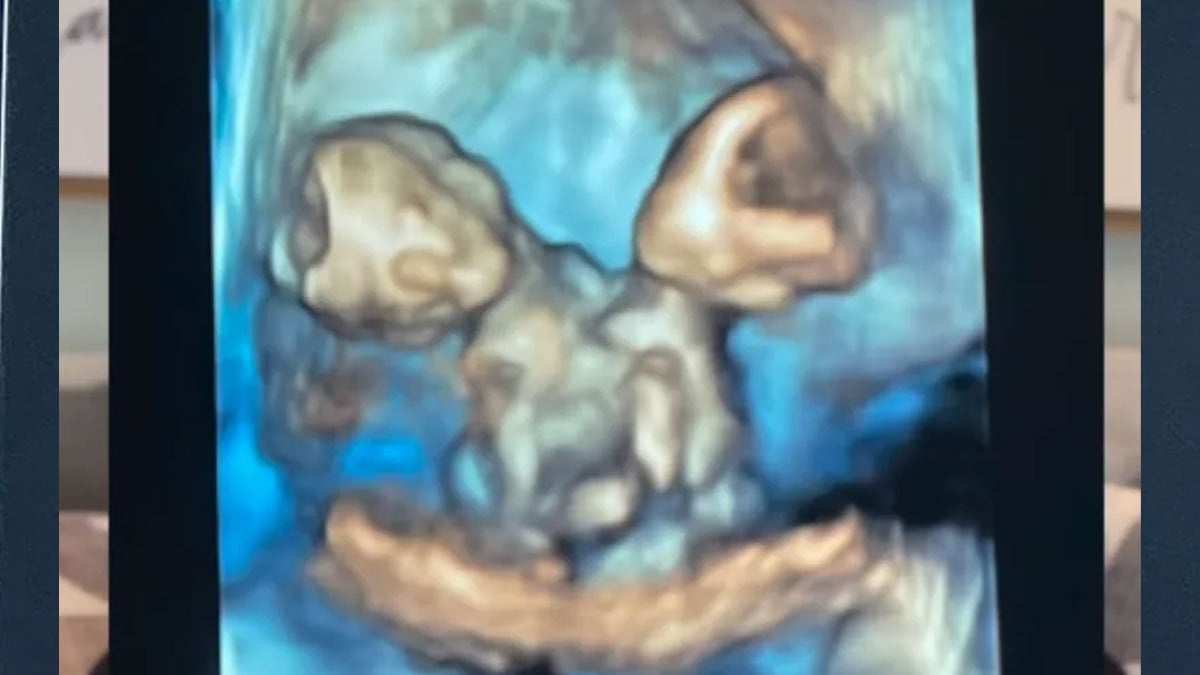

Kısa süre sonra Nicole, şiddetli karın ağrısıyla hastaneye kaldırıldığında gerçek ortaya çıktı. Anne adayı, aynı kalbi, karaciğeri, bağırsakları, diyaframı ve göbek kordonunu paylaşan ikiz kız bebeklere hamileydi.

Nicole, 32. haftada sezaryenle ikizlerini dünyaya getirdi. Maria Therese ve Rachel Clare isimleri verilen bebekler, doğum anında farklı tepkiler verdi.